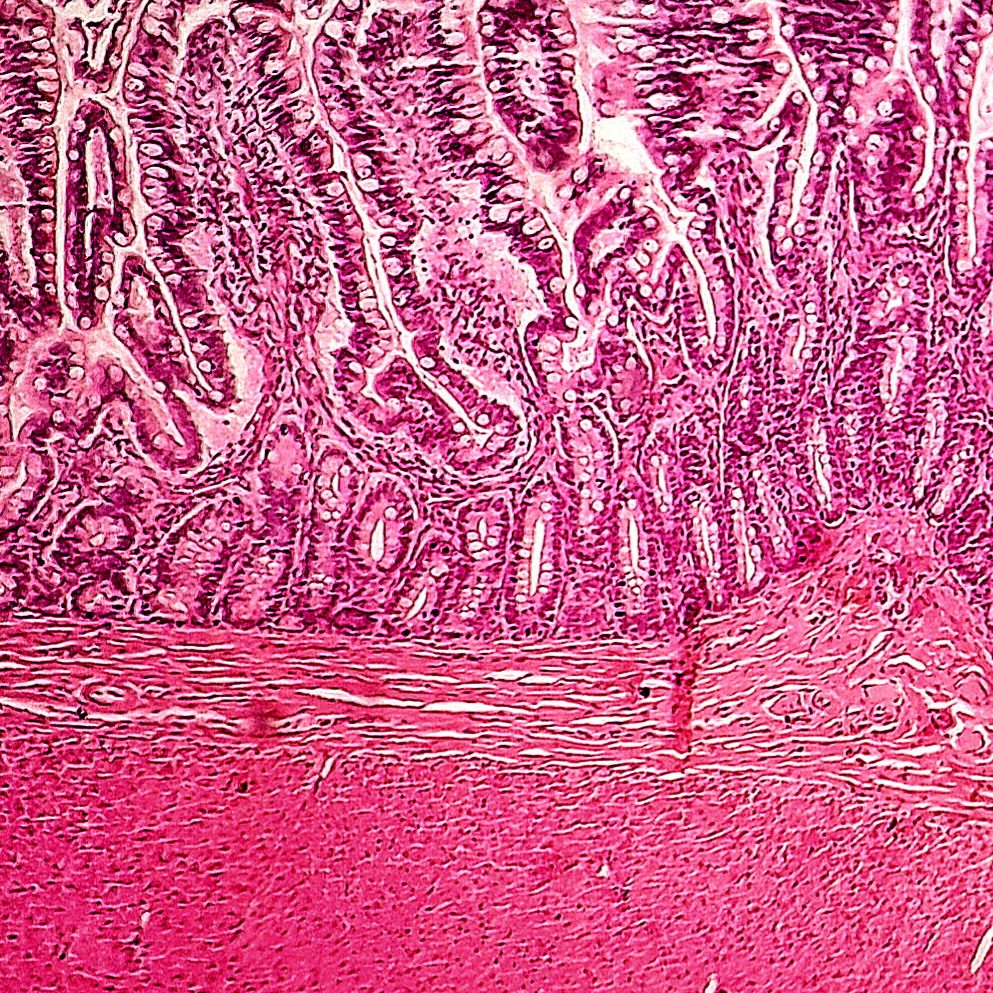

Sistema Digestivo

O sistema digestivo é composto pelo trato digestivo, incluindo; a cavidade oral, esôfago, estômago, intestino delgado e o grosso, além de glândulas associadas. O tubo digestivo é formado por quatro camadas principais: camada mucosa mais interna, reveste o lúmen e é composta por epitélio, camada submucosa composta por tecido conjuntivo denso contendo vasos sanguíneo, linfáticos e nervosos, a camada muscular, apresentando fibras musculares lisas e a camada serosa, que é uma camada externa que envolve o trato digestivo. As glândulas salivares disposta contam com; sublinguais, submandibulares e a parótida.